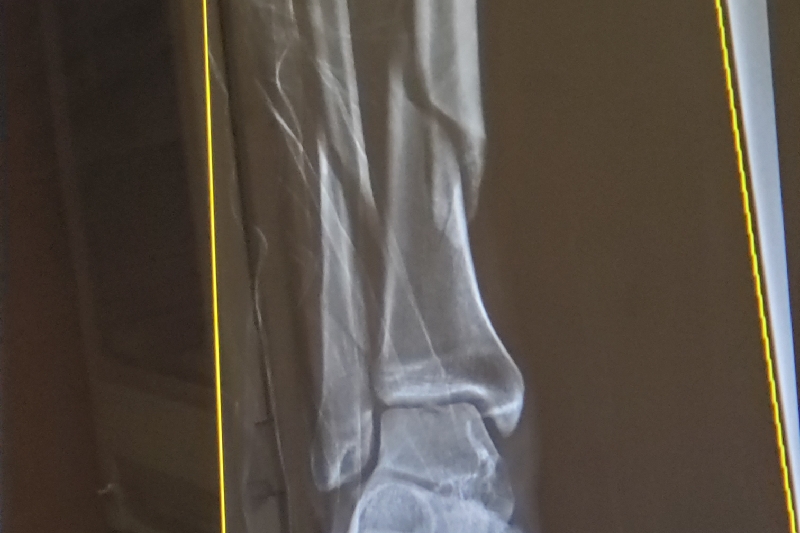

Hello I am Scott Blackman. As many of you may or may not know, 2019 was a rough year for me. I suffered a variety of setbacks both legally, financially and physically. Recently just before the holidays i suffered a severe break in my right leg. It was a break that affected both my tibia (shin bone), and the fibula snapping them both in two. I had a very successful surgery and have been recovering very well. As many of you have experienced before I am sure, however with limited compensation from insurance, and the high cost of medical procedures in general added to time missed from work I have fallen way behind on my normal bills. I have recently returned to work, but it will be awhile before I will be back to normal birth physically and financially. I am behind on my rent, have maxed out credit cards and borrowed from my company all to try and keep me afloat. My personal responsibility after insurance for surgery and ambulance e.t.c already is right around $6,000 and I expect there will be more fees trickling in. Gaining partial disability pay from my insurance company is very little and is a long drawn out process that will not help much. It is with great humbleness that I reach out to you and ask for assistance. The holidays are always brutal on people's pocketbooks which I am totally aware, so the timing couldn't be worse, but I am truly humbled and thankful for whatever you may be able to contribute. Thank you!!